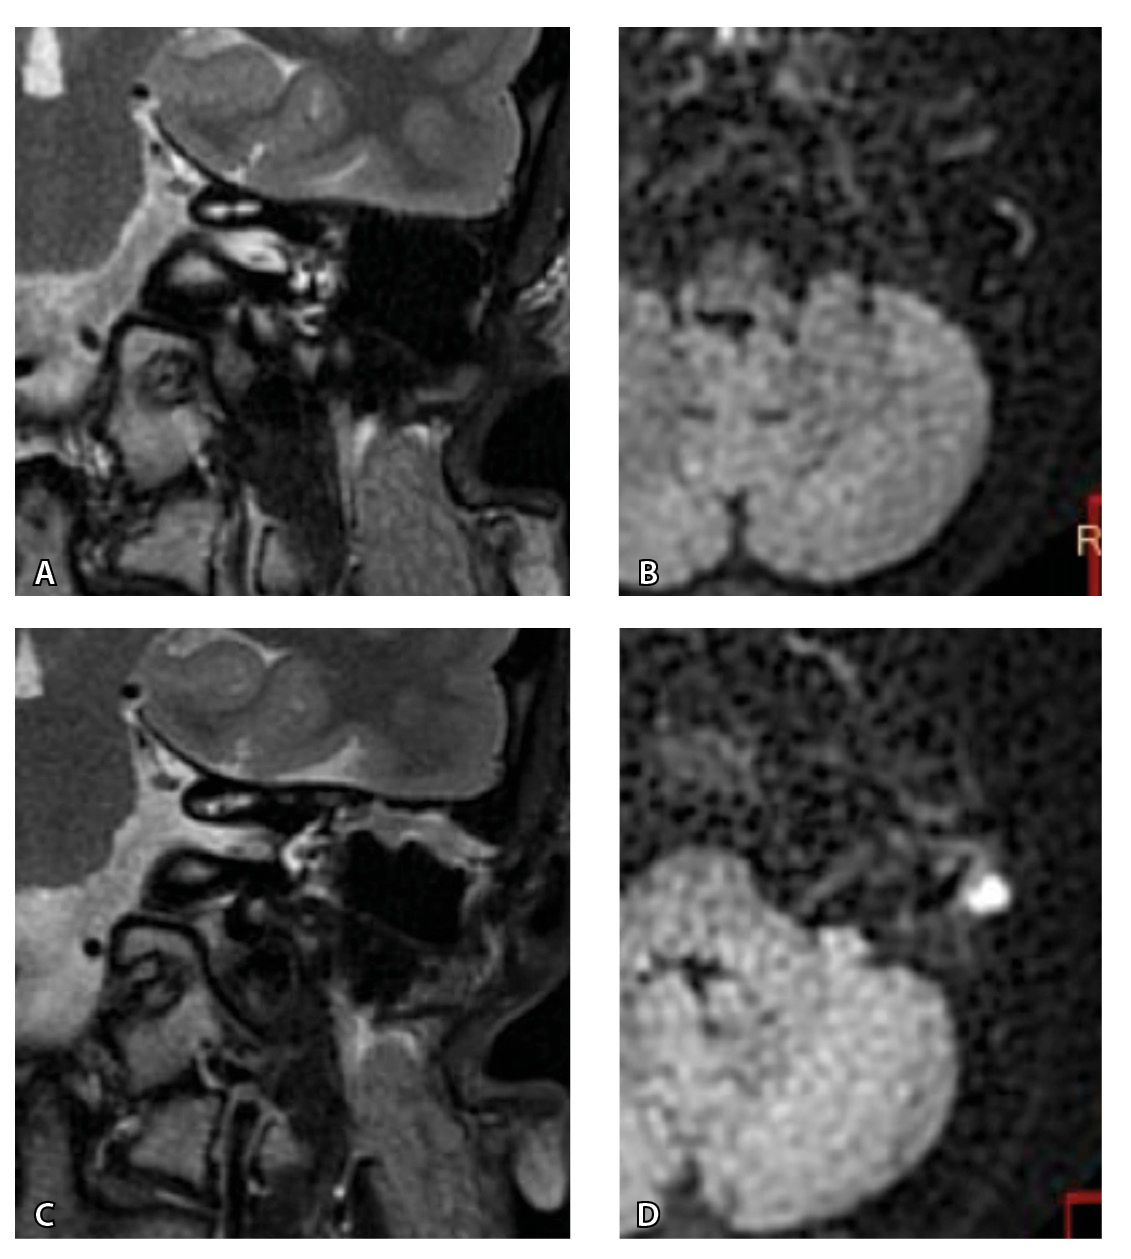

Одним из интересных встреченных нами случаев ложноположительных МР-результатов было грибковое поражение послеоперационной полости с отрицательной динамикой в течение 16 месяцев (рис. 5).

Рис. 5. При первичном послеоперационном исследовании на Т2-взвешенных изображениях во фронтальной плоскости определяется пневматизированная послеоперационная полость (А), без признаков ограничения магнитно-резонансной диффузии (Б). При контрольном исследовании – отрицательная динамика с появлением пристеночных разрастаний вдоль стенок послеоперационной полости (В), ограничивающих магнитно-резонансную диффузию (Г). Данные интерпретированы как рецидив холестеатомы. При оперативном лечении и последующей гистологии – грибковое поражение среднего уха